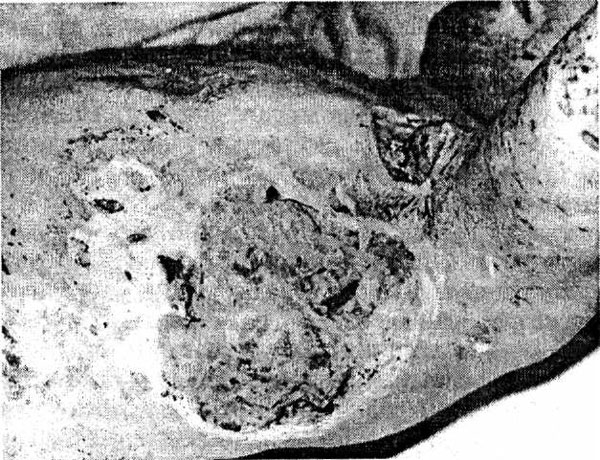

Отмечается следующая последовательность процессов заживления гнойных ран. Вначале происходит очищение очага воспаления от всех некротизированных клеток, тканей, сгустков крови и т. д. После этого на отдельных участках стенок гнойной полости появляются разрастания клеток в виде красных узелков, которые, постепенно увеличиваясь в количестве и размерах, покрывают все стенки и дно раны. Эти красные узелки состоят из молодых соединительных клеток (фибробластов) и называются грануляционной тканью, которая заполняет всю полость гнойного очага до поверхности кожи (рис. 1). После этого кожный эпителий, разрастаясь, покрывает грануляции, клетки которой (фибробласты) постепенно образуют волокнистую соединительную ткань – так образуется рубец.

Рис. 1. Обширные гранулирующие раны грудной клетки